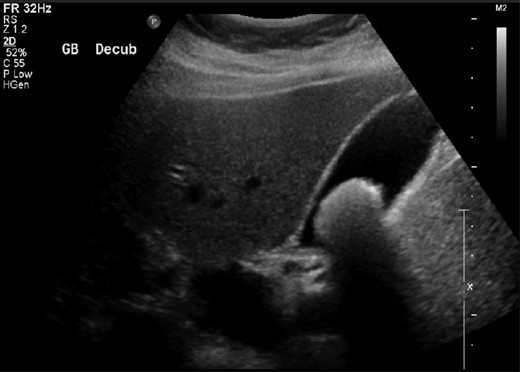

Her investigation showed a white cell count of 8 × 109/L, haemoglobin of 12 g/dL, bilirubin of 9 mmol/L, alkaline phosphatase of 84 IU/L, GGT of 17 IU/L, amylase of 46 U/L, C-reactive protein of 6 mg/dL. She had a previous ultrasound (US) abdomen in July 2014 demonstrating a single large gallstone (Fig. 1). The common bile duct (CBD) calibre was normal.